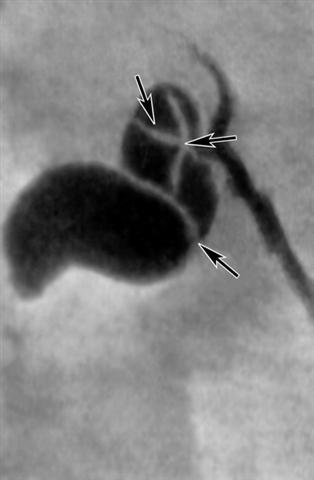

Рис. 1. Холецистограмма при хроническом некалькулезном холецистите: желчный пузырь деформирован имеет перетяжки, обусловленные перипроцессом (указаны стрелками).